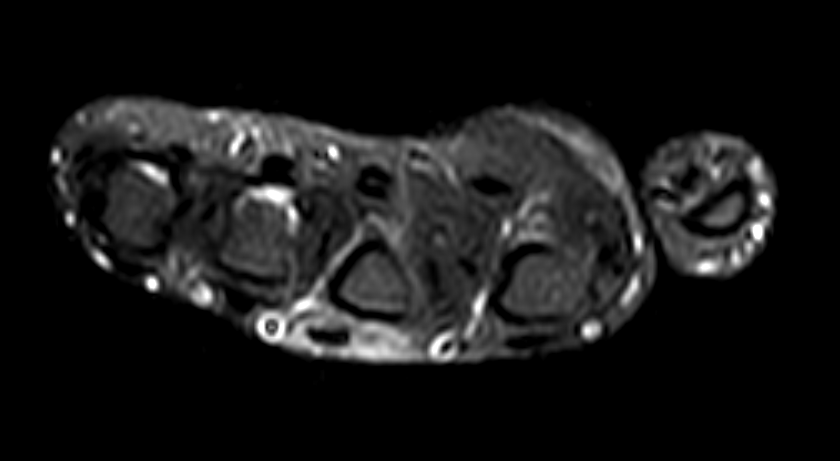

A 1-month-old male infant presented with complaints of midline swelling in the postero-superior region of head.